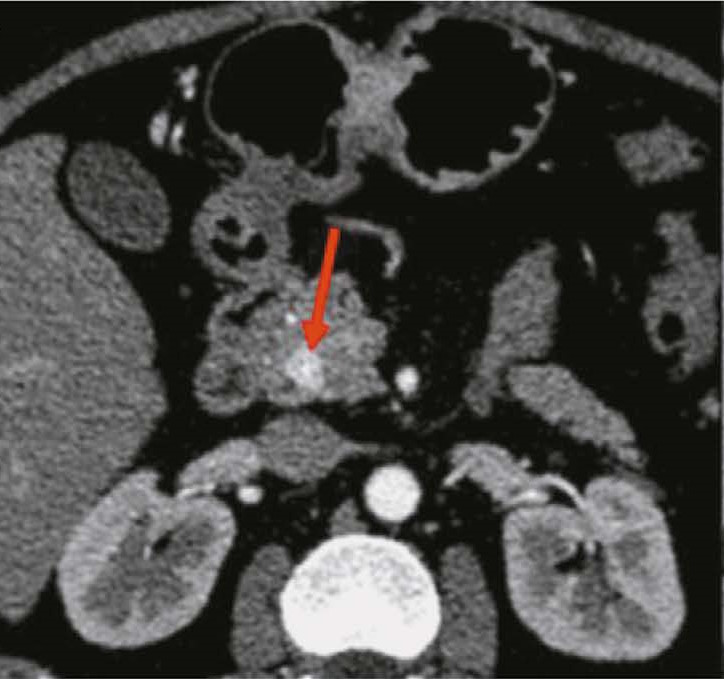

Hypoplasia of the inferior vena cava with hypertrophic azygos/hemiazygos and collateral venous circles of the abdomen: a case report

Abstract

Hypoplasia of the inferior vena cava is a rare congenital vascular defect with various forms; thus, identifying a specific anatomical variant in the literature is challenging. In some cases, the inferior vena cava may also be interrupted. Herein, we present a unique case of of an unknown subrenal hypoplasia of the inferior vena cava with azygos and hemiazygos hypertrophy and the creation of several collateral circles, particularly in the anterior wall of the abdomen, in an asymptomatic 75 year old man. This report not only describes this unusual instance but also quickly demonstrates the variations of the venous system in the abdomen, particularly on the right side, and the inferior vena cava and the azygos system, and explains the significance of imaging in recognizing vascular anomalies. The case was explored using a multiphase computed tomography technique, which correctly identified this complex vascular anomaly. The patient had never experienced symptoms associated with the same vascular defect previously. Moreover, his symptoms did not appear to be related; therefore, a periodic follow up was recommended.

902-910